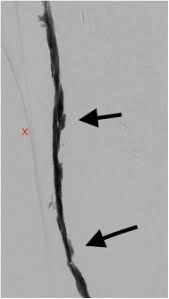

A comparative evaluation of polytetrafluoroethylene umbilical vein and saphenous vein bypass grafts for femoral-popliteal above-knee revascularization. Graft occlusion is commonly the result of stenosis at the anastomosic sites. It was applied to a series of 16 leg bypass patients to dissect totally endoscopically the greater saphenous vein for either translocated or in situ procedures. These results are comparable to or better than those reported for autogenous vein shunts created by removal and reversal of the. The first image demonstrates the stump of an occluded right femoropopliteal artery bypass graft. In the current endovascular era the femoral-popliteal bypass remains one of the most common open vascular operations. The precise role of thrombolysis in the treatment of bypass graft thrombosis is somewhat controversial.